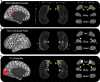

The hippocampus supports multiple cognitive functions including episodic memory. Recent work has highlighted functional differences along the anterior-posterior axis of the human hippocampus, but the neuroanatomical underpinnings of these differences remain unclear. We leveraged track-density imaging to systematically examine anatomical connectivity between the cortical mantle and the anterior-posterior axis of thein vivo human hippocampus. We first identified the most highly connected cortical areas and detailed the degree to which they preferentially connect along the anterior-posterior axis of the hippocampus. Then, using a tractography pipeline specifically tailored to measure the location and density of streamline endpoints within the hippocampus, we characterised where these cortical areas preferentially connect within the hippocampus. Our results provide new and detailed insights into how specific regions along the anterior-posterior axis of the hippocampus are associated with different cortical inputs/outputs and provide evidence that both gradients and circumscribed areas of dense extrinsic anatomical connectivity exist within the human hippocampus. These findings inform conceptual debates in the field and emphasise the importance of considering the hippocampus as a heterogeneous structure. Overall, our results represent a major advance in our ability to map the anatomical connectivity of the human hippocampusin vivo and inform our understanding of the neural architecture of hippocampal-dependent memory systems in the human brain.